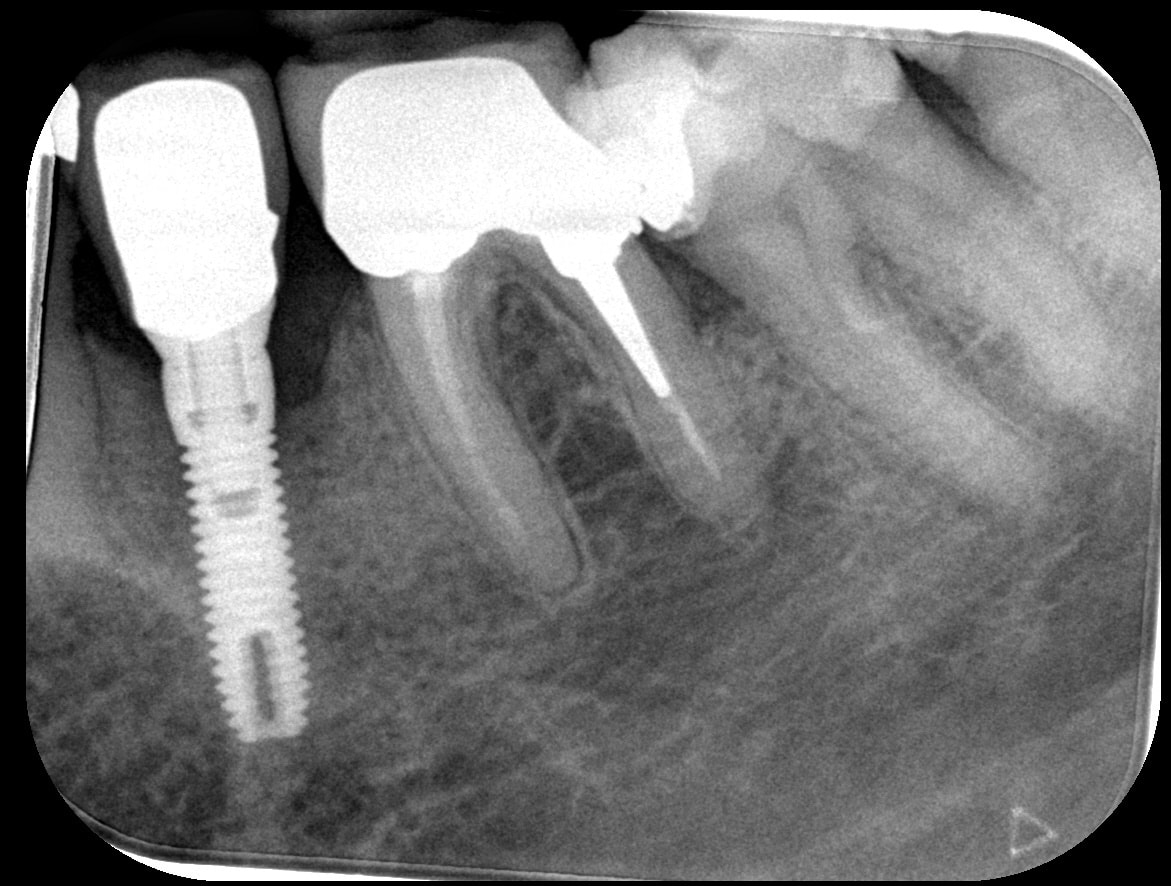

Résultat de l’arrêt du tabac chez un patient

Cas spectaculaire :

pas de traitement entre les deux radios sauf bains de bouche + brossettes et arrêt de la cigarette !